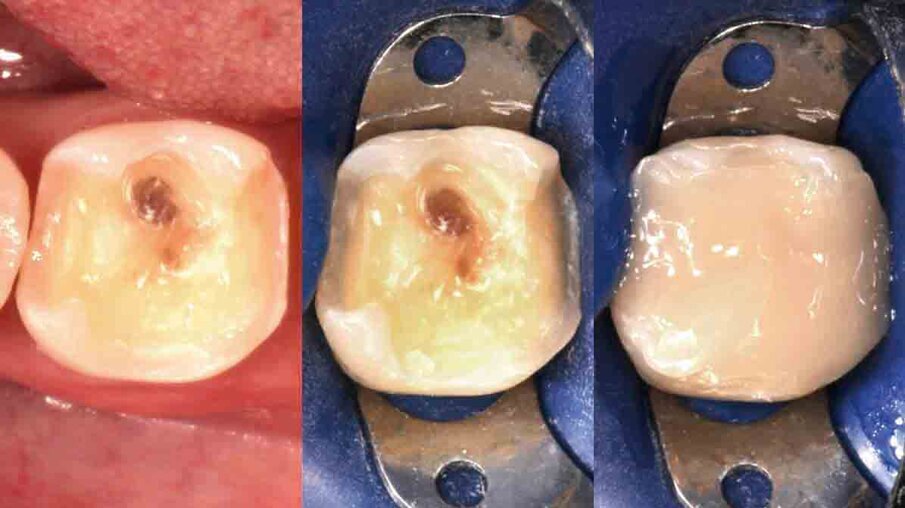

Fig. 3: Upon removal of the old filling, it becomes clear that a crown is needed to ensure the required stability. The tooth is built up with 3M™ Filtek™ Bulk Fill Posterior Restorative, which may be placed in conjunction with 3M™ Single Bond Universal Adhesive and in increments of up to 5 mm.